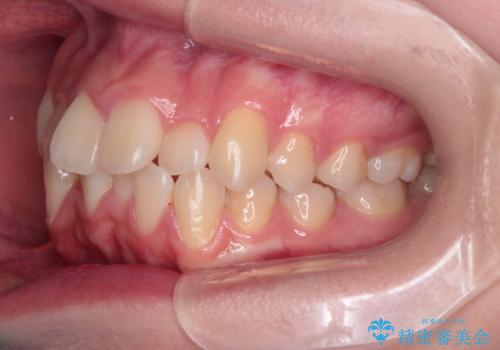

【インビザライン】前歯の凸凹を非抜歯で治療

- 前歯の凸凹を主訴の来院されました。

奥歯を後ろの方に移動させるために矯正用のアンカースクリューを使いながら治療をおこないました。

患者さんの都合により、マウスピースの装着時間が不足したため、途中からワイヤーにて治療を行いました。